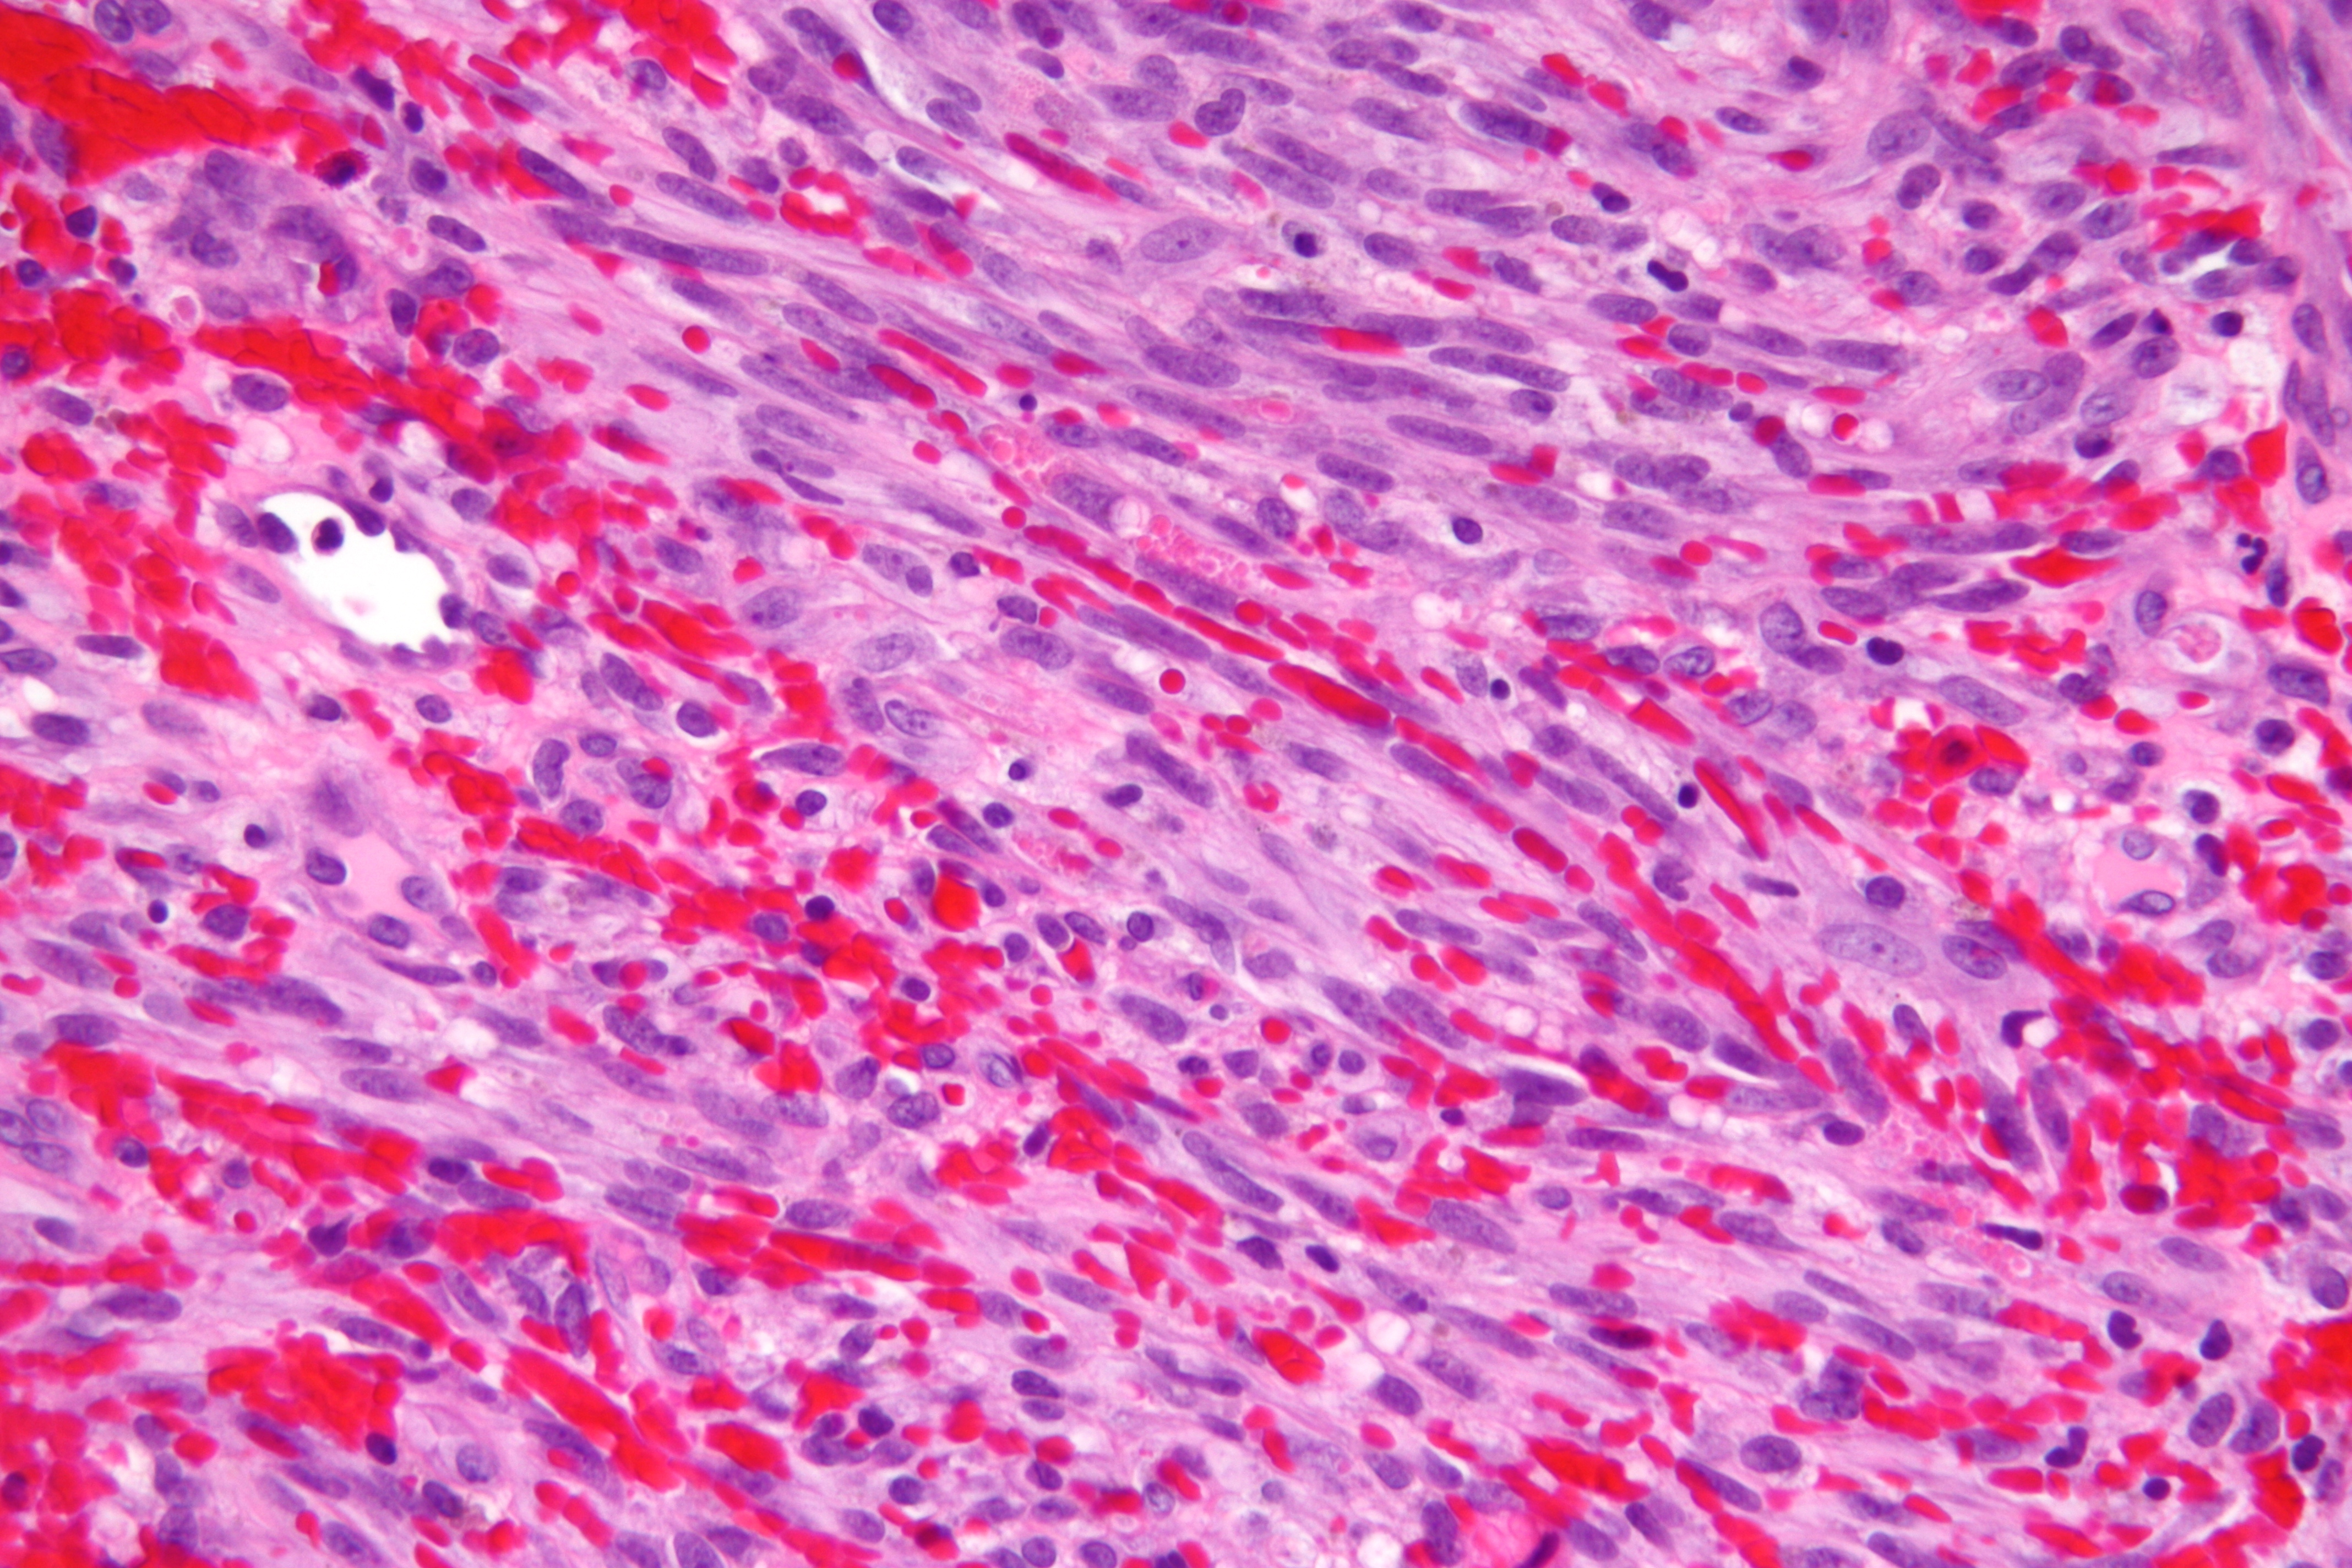

1872년 모리츠 카포시는 혈관 종양[4] (원래는 "특발성 다발성 피부 색소 육종")을 처음 기술했으며, 이는 후에 카포시 육종(KS)으로 명명되었다.[52] 초기에는 유대인과 지중해 지역 사람들에게 드물게 발생하는 종양으로 여겨졌으나, 나중에 사하라 사막 이남 아프리카 지역에서는 매우 흔한 질병임이 밝혀졌다. 이러한 배경 속에서 1950년대에 이 종양이 바이러스 감염에 의해 발생할 수 있다는 가설이 처음 제기되었다.

감염은 특히 면역 저하 환자에게 문제가 되는데, 화학 요법을 받는 암 환자, AIDS 환자, 장기 이식 환자는 모두 감염 징후를 보일 위험이 높다. 카포시 육종은 KSHV에 감염된 사람이 에이즈, 의료 치료 또는 매우 드물게 노화로 인해 면역 저하가 되면 발생한다.

KSHV는 다음과 같은 네 가지 질병의 알려진 원인 물질이다:[27][28]